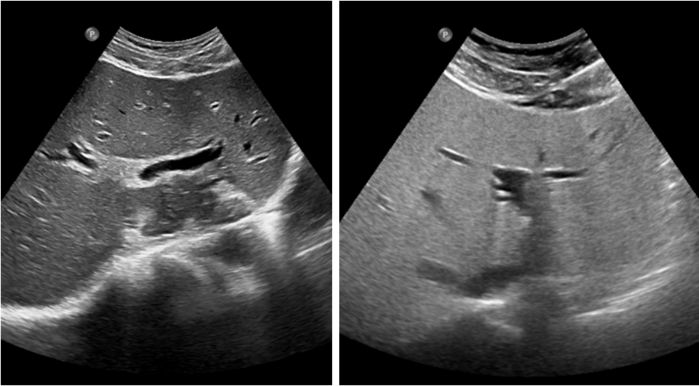

| ▲ 정상간과 지방간 |